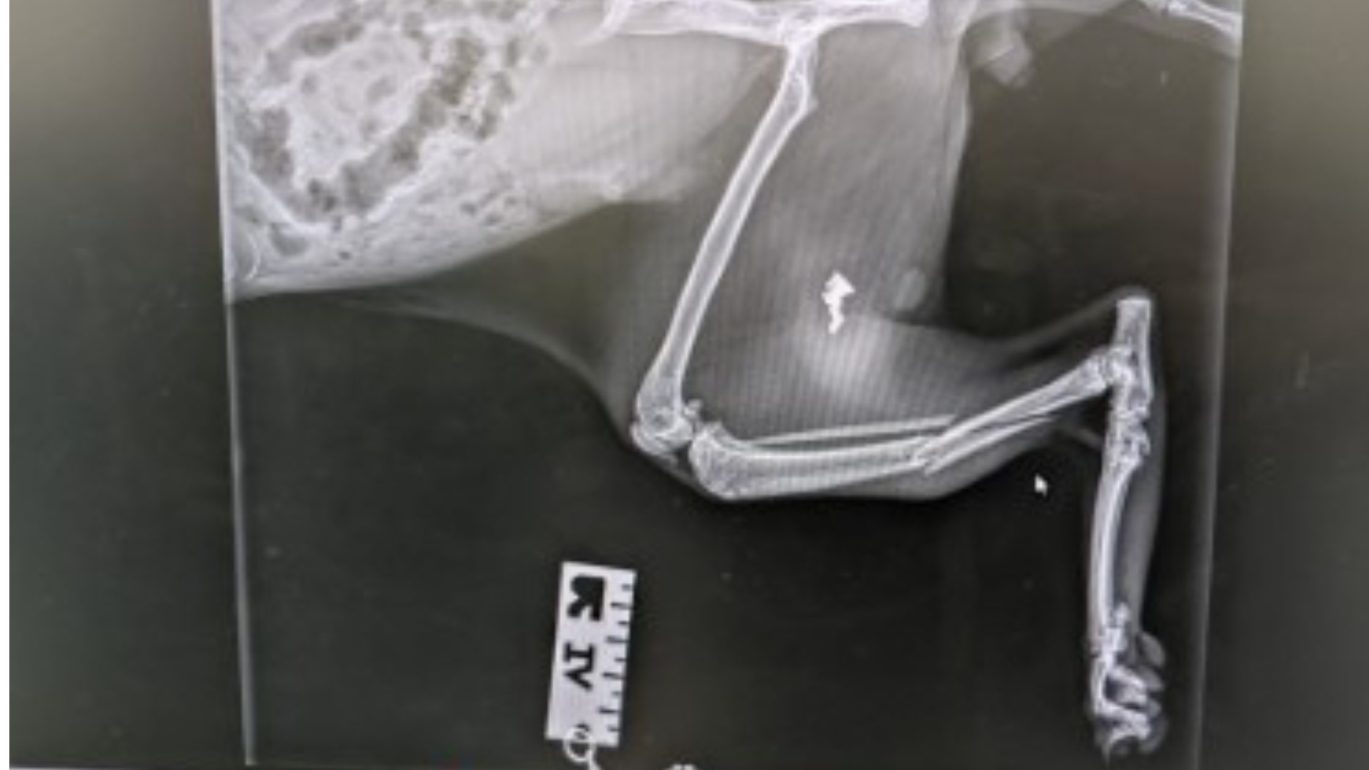

Leo’s owner rushed him to the emergency vets where they found three significant fractures to his right leg and the x-ray showed a bullet was lodged in his thigh. After careful assessment by the vet, it was determined that the only way forward was to amputate Leo’s injured leg from the hip joint.